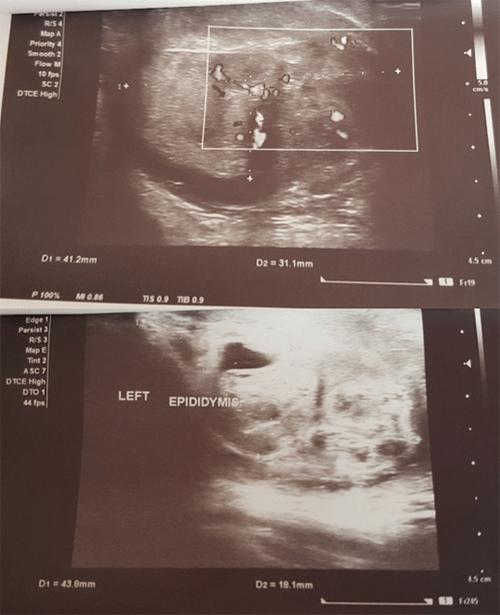

Laboratory investigations showed a total leucocyte count (TLC) of 6,300/mm3, hemoglobin 12.9 gm/dl, and erythrocyte sedimentation rate (ESR) measuring 17 mm/hr. Other biochemical tests were normal, with lactic acid dehydrogenase (LDH) at 292 units/L, alpha-fetoprotein at 5.14 ng/mL, and beta HCG at 2.31 mUI/mL. Routine urine test was normal, and the Mantoux test was negative. A chest X ray, as well as ultrasonography (USG) of the abdomen and pelvis, were normal. Sputum acid-fast bacilli (AFB) was negative. USG of the scrotum showed a heterogenous area at the posterior part of the testes measuring 41.2 × 31.1 mm with vascularity within it with minimal fluid in the testicular sac and epididymal head measuring 43.8 × 18.1 mm with vascularity with a thickened scrotal wall (Figure 1).

Figure 1. Ultrasonography of Left Scrotum. Published With Permission

Scans show heterogenous area at posterior part of testes measuring 41.2 × 31.1 mm with vascularity within it with minimal fluid in testicular sac and epididymal head measuring 43.8 × 18.1 mm with vascularity with thickened scrotal wall.